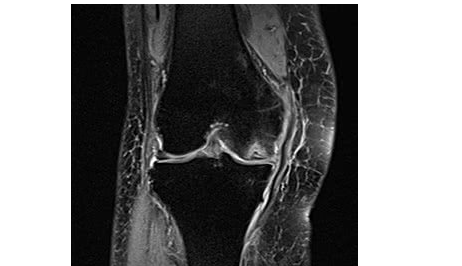

治疗2个月后的変化

患者称走路速度比以前快了。

因为走得比以前多,所以有点疼,但是没有治疗前那么严重。